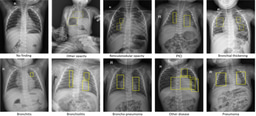

The dataset contains more than 100,000 chest X-ray scans that were retrospectively collected from two major hospitals in Vietnam. Out of this raw data, we released 18,000 images that were manually annotated by a total of 17 experienced radiologists with 22 local labels of rectangles surrounding abnormalities and 6 global labels of suspected diseases. The released dataset is divided into a training set of 15,000 and a test set of 3,000. Each scan in the training set was independently labeled by 3 radiologists, while each scan in the test set was labeled by the consensus of 5 radiologists. All images are in DICOM format and the labels from training and test sets are made publicly available.

Examples of CXRs with radiologist’s annotations. Abnormal findings (local labels) marked by radiologists are plotted on the original images for visualization purposes. The global labels are in bold and listed at the bottom of each example.